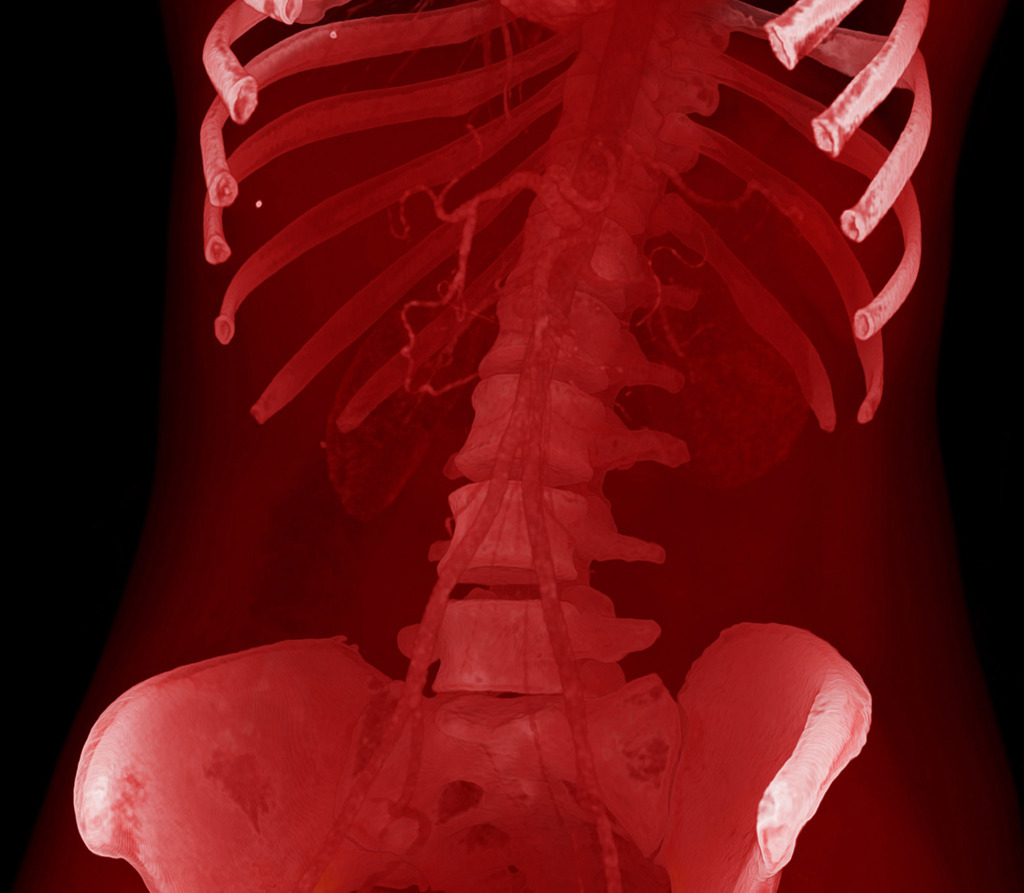

The program for processing radiological images (DICOM archives) allows you to create and look at a three-dimensional image from different angles.

If you change the location of the virtual lens, thereby changing the perspective, you can get such images.

No. Tissues with different densities are best suited to visualisation by CT imaging.

Lungs and heart, bones and muscles or organs injected with a contrast agent reveal the best structure and anatomy.